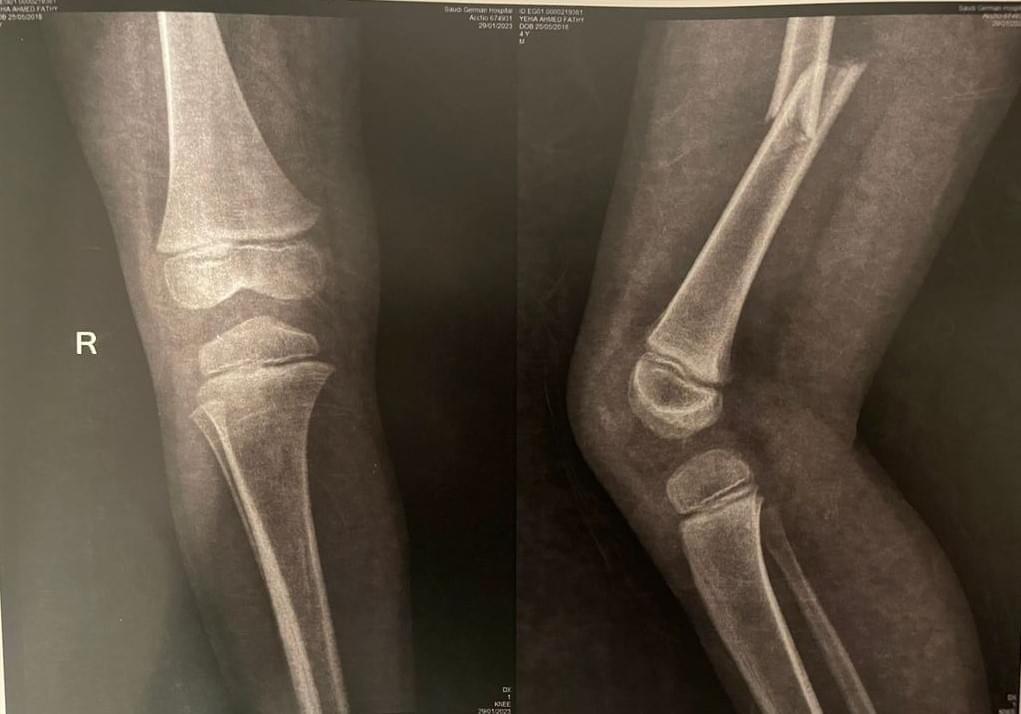

وقال والد الطفل أحمد فتحي لـ القاهرة 24: أصيب الطفل في كسر في الفخذ، وأجريت له عملية تركيب مسامير، وسيبدأ الطفل في رحلة العلاج الطبيعي، وبعد 4 شهور سيتم إجراء عملية أخرى له.

وأخبرت المستشفى والدة الطفل أنه مصاب بكسر في عظمة الفخذ، ويحتاج إلى عملية جراحية، ومن بعدها علاج طبيعي ويحتاج إلى عملية أخرى.